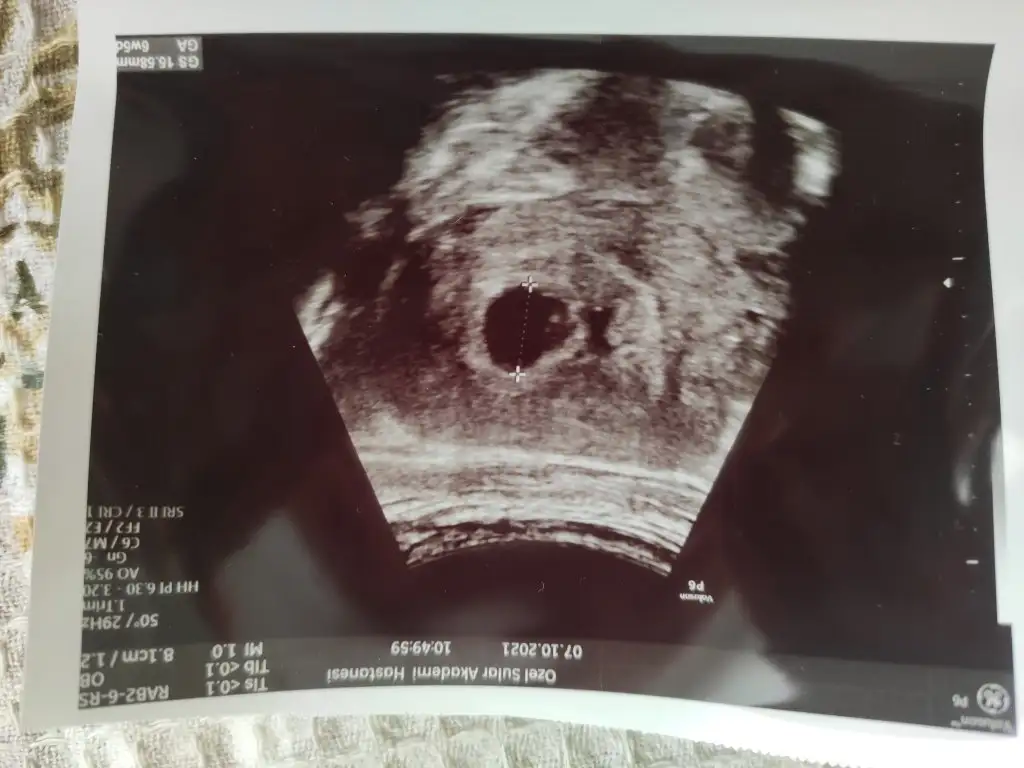

Selam kızlar geldim hastaneden, maalesef biraz hayal kırıklığı var kalp atışı dinletmedi. Kese ve bebek var kalp atışı için 15 gün sonra gel dedi, hocam bu haftalarda duyulması gerekmez mi dedim yok henüz duyulmaz dedi. Ama arkadaşlar duymuş dedim, herkesin döllenme zamanı farklıdır dedi, ama ben ovulasyon takibi yaptım hocam dedim, artık ters ters bakmaya başlayınca sustum 😂 kadın herşey gayet normal dedi pozitif konuştu ama benim moralim bozuk tabi, o kadar bekledim 😭 kontrol süresi 10 günmüş hastanede, 15 gün sonra tekrar gidip tekrar muayene ücreti ödeyecem bir de 🤣 neyse en azından dış gebelik falan değil ama işte ne yapalım ☺️